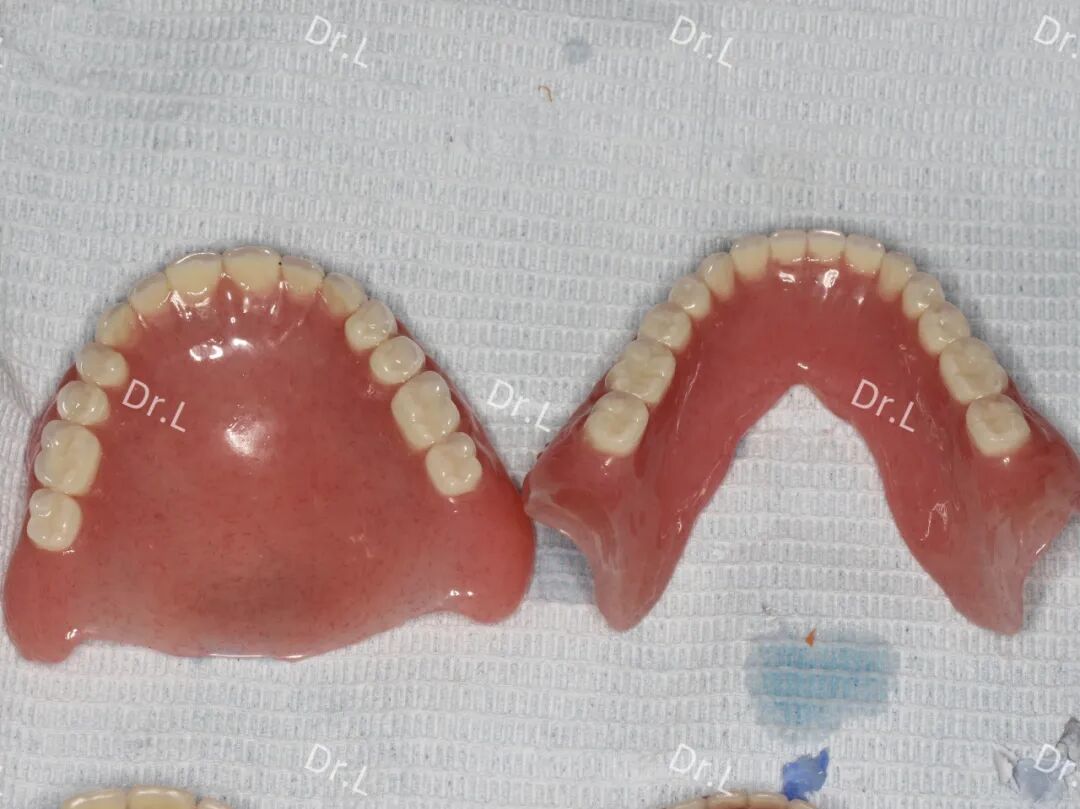

成品

吸附性全口义齿(上)与普通全口义齿(下)对比——更轻便 异物感小